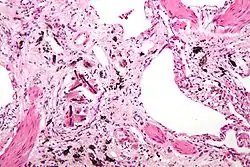

Asbestosis is the scarring of lung tissue (beginning around terminal bronchioles and alveolar ducts and extending into the alveolar walls) resulting from the inhalation of asbestos fibers. There are two types of fibers: amphibole (thin and straight) and serpentine (curly). All forms of asbestos fibers are responsible for human disease as they are able to penetrate deeply into the lungs. When such fibers reach the alveoli (air sacs) in the lung, where oxygen is transferred into the blood, the foreign bodies (asbestos fibers) cause the activation of the lungs' local immune system and provoke an inflammatory reaction dominated by lung macrophages that respond to chemotactic factors activated by the fibers.[20] This inflammatory reaction can be described as chronic rather than acute, with a slow ongoing progression of the immune system attempting to eliminate the foreign fibers. Macrophages phagocytose (ingest) the fibers and stimulate fibroblasts to deposit connective tissue.

Due to the asbestos fibers' natural resistance to digestion, some macrophages release inflammatory chemical signals, and other macrophages are killed, releasing reactive oxygen species and activating transcription factors, like NF-kB, which amplify the expression of pro-inflammatory cytokines.[21] These inflammatory chemical signals attract further lung macrophages and fibrolastic cells that synthesize fibrous scar tissue, which eventually becomes diffuse and can progress in heavily exposed individuals. This tissue can be seen microscopically soon after exposure in animal models. Some asbestos fibers become layered by an iron-containing proteinaceous material (ferruginous body) in cases of heavy exposure where about 10% of the fibers become coated. Most inhaled asbestos fibers remain uncoated. About 20% of the inhaled fibers are transported by cytoskeletal components of the alveolar epithelium to the interstitial compartment of the lung where they interact with macrophages and mesenchymal cells. The cytokines, transforming growth factor beta and tumor necrosis factor alpha, appear to play major roles in the development of scarring inasmuch as the process can be blocked in animal models by preventing the expression of the growth factors.[22][23] The result is fibrosis in the interstitial space, thus asbestosis.

Extensive fibrosis of pleura and lung parenchyma -